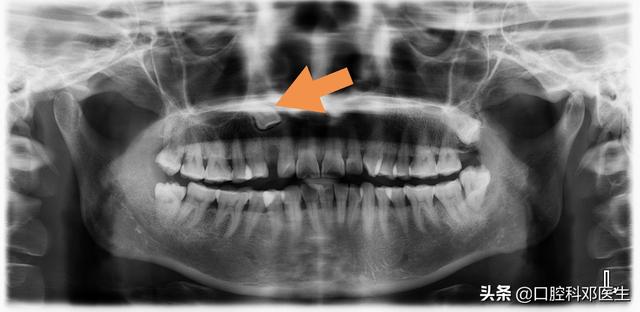

5.埋伏牙、阻生牙

埋伏牙、阻生牙就是我们常说的智齿,还包括一些虎牙,如不拔除,常引起经常发炎,长囊肿或者肿瘤。